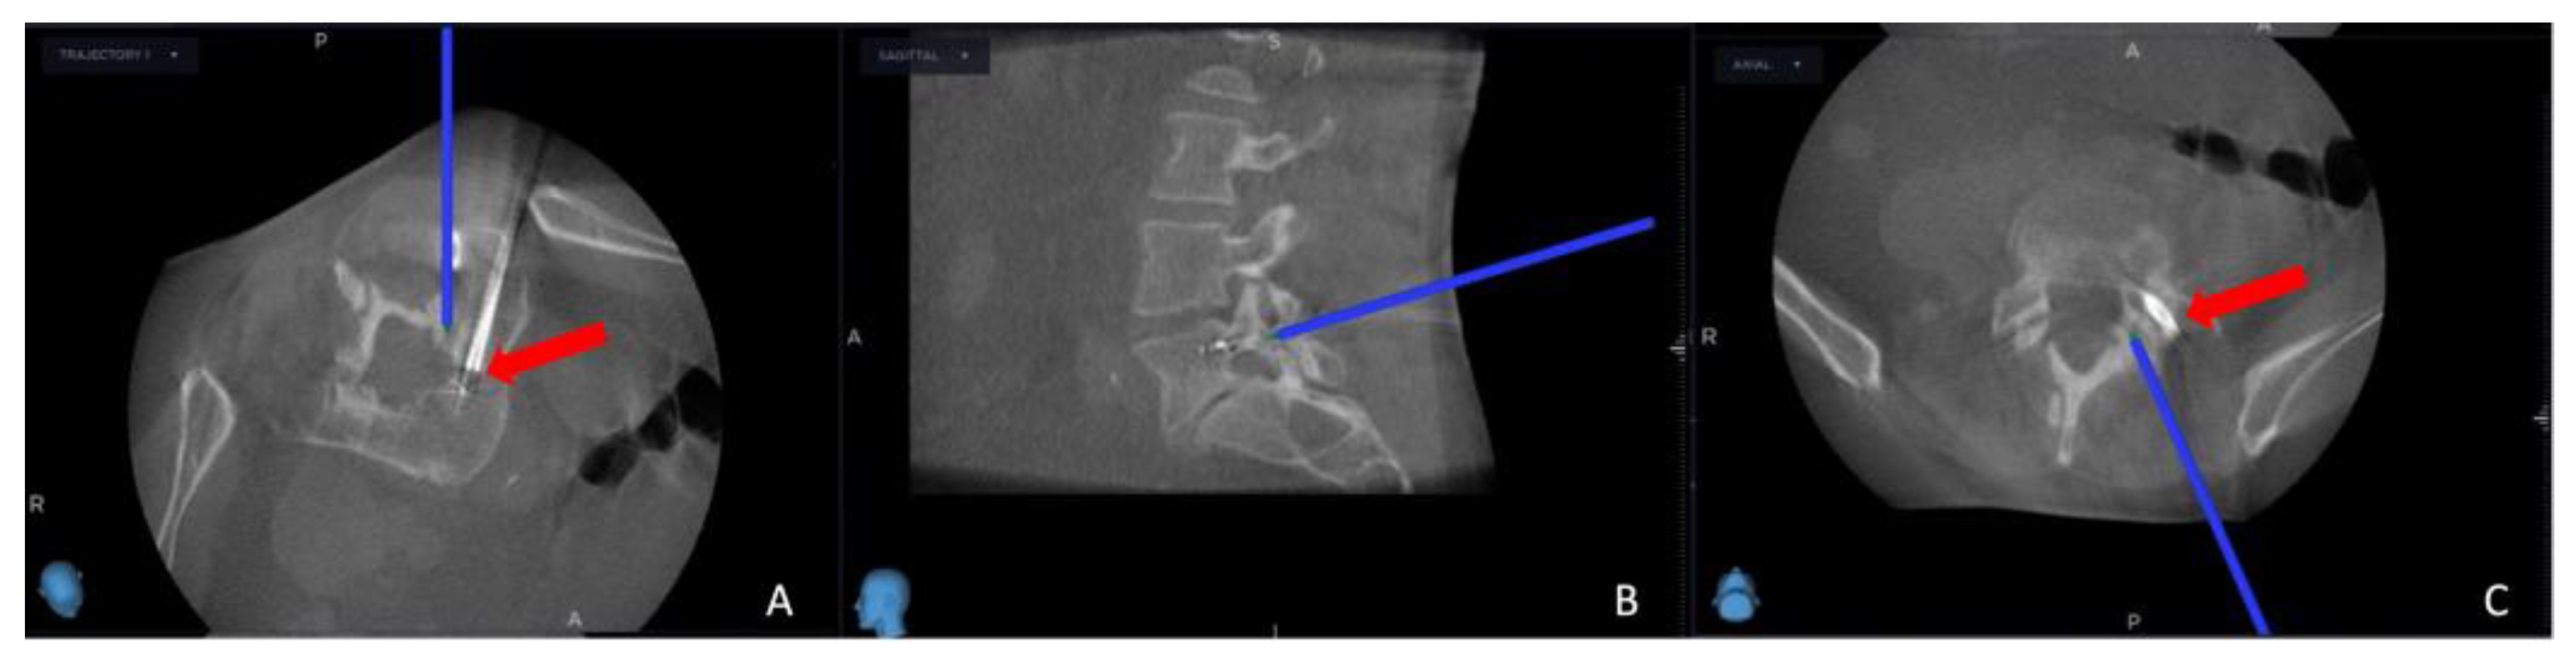

Figure 3. Second intra-operative CBCT scan in the trajectory angled axial view (A), sagittal view (B), and axial view (C). The blue projection line shows the thermostat location, and the red arrow shows the electrode position.

Successful needle biopsy sampling was confirmed if the needle biopsy channel's position in the second O-arm scan matched the plan selected in the MRI scan, and the sample was sent to the pathology department for tumor typing. Subsequently, the electrode's and the thermostat's placement were verified by cross-referencing the registered instrument with the merged image (Figure 3). Thermocoagulation was set at 70 °C and lasted for 7 minutes, and the process halted upon reaching a thermostat temperature of 39.5°C. Finally, the Spine Stealth Air reference frame was removed. In cases deemed necessary, Percutaneous Vertebroplasty (PVP) was performed.